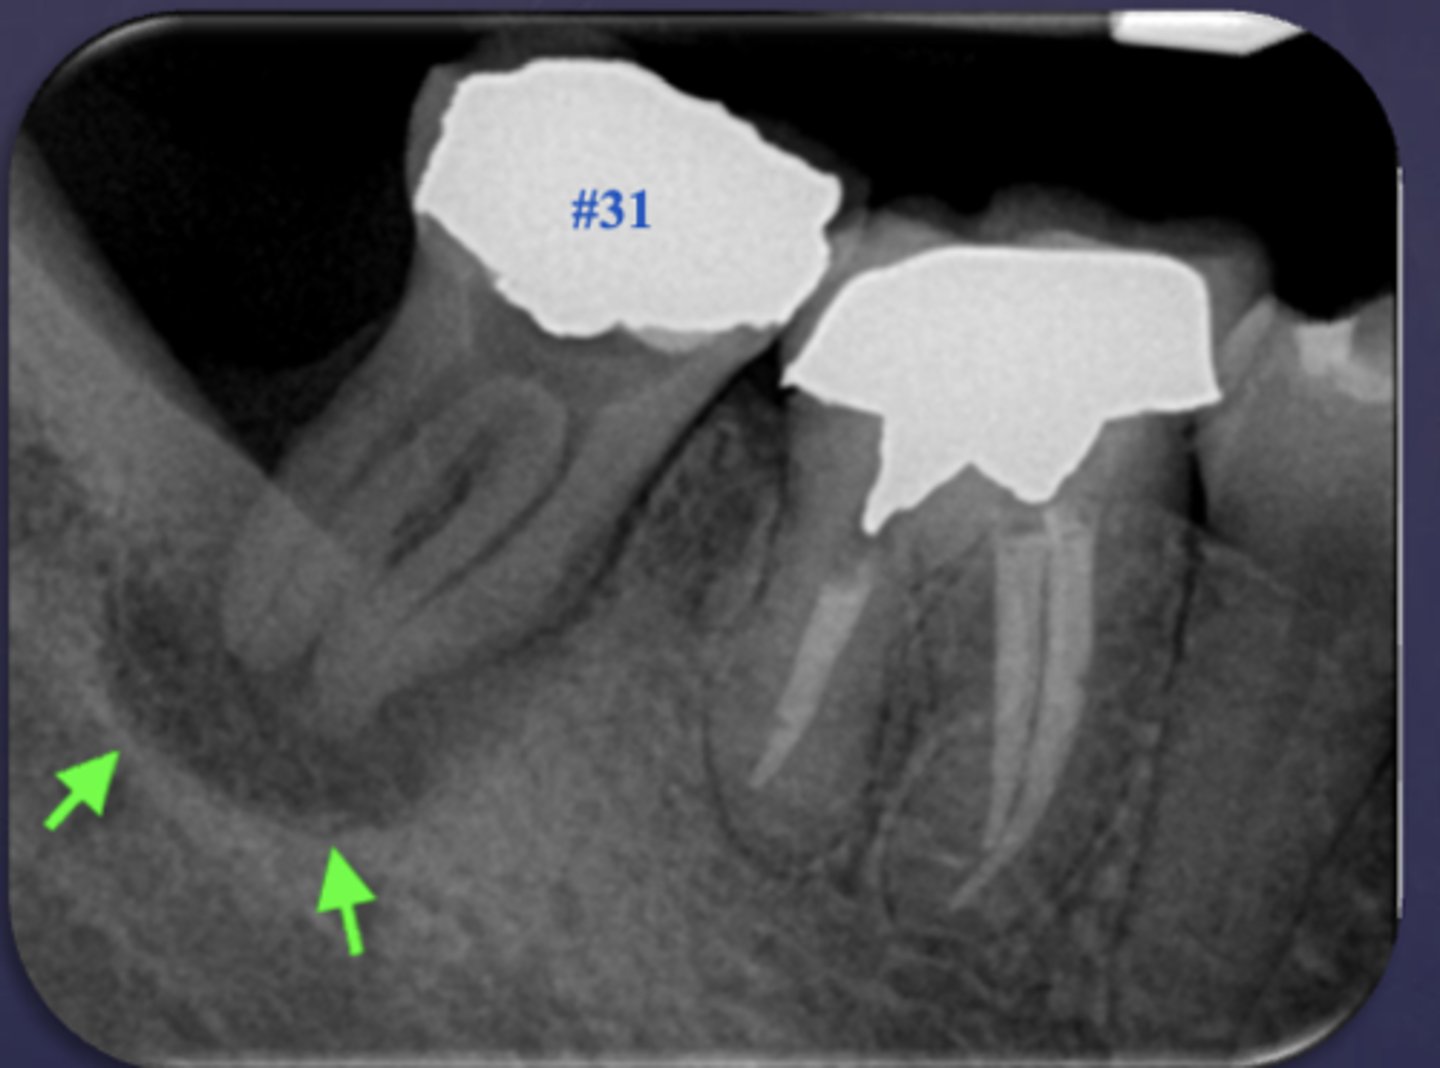

What is the black arrow pointing at?

sequestrae

What is the white arrow pointing at?

periosteal reaction

periosteal reaction (increased bone density)

sequestra

What phase of osteomyelitis does this show?

acute (multiple sequestrae)